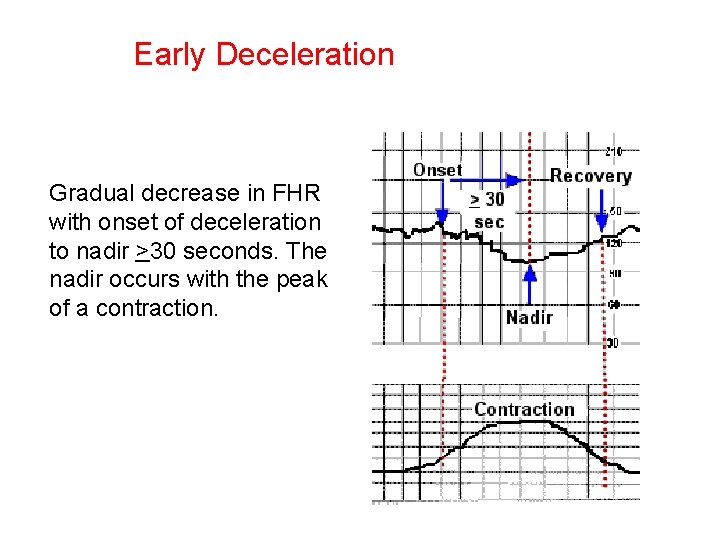

Early Deceleration Gradual decrease in FHR with onset of deceleration to nadir >30 seconds. The nadir occurs with the peak of a contraction.